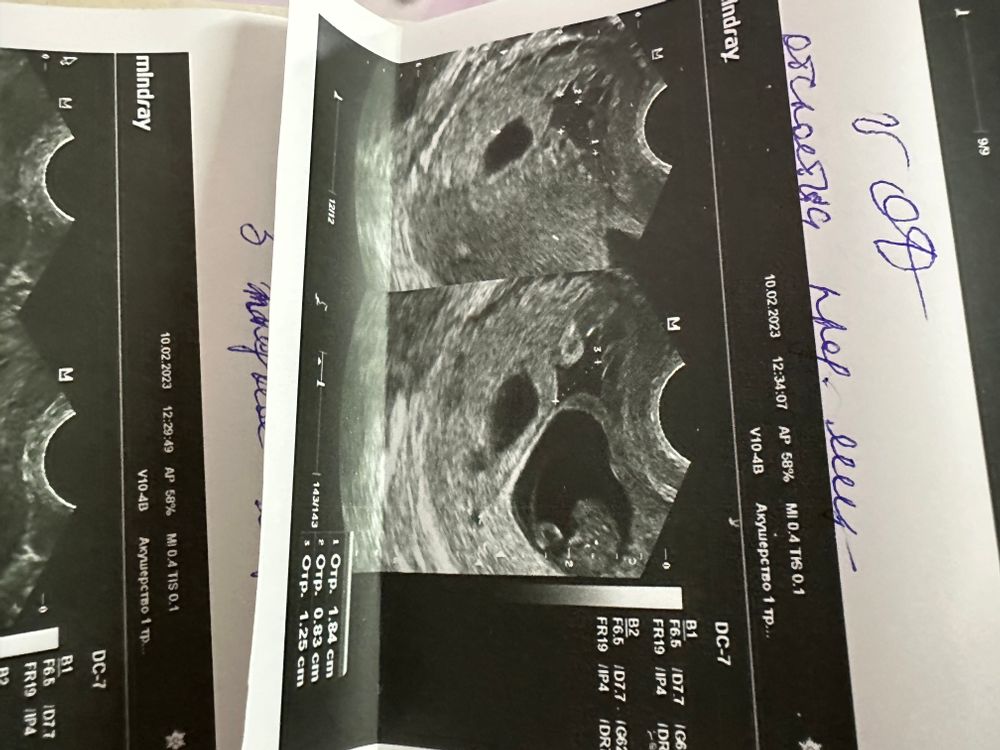

Отслойка на 9 неделе

девочки, кто знает и разбирается. Нашли отслойку. Переживаю так… в стационаре толком ничего не сказали

Получается двое эмбриончиков?

Я думаю что у третьего появиться сб на днях по размерам он чуть чуть отстаёт, и вообще как врач может писать Аноэмбриония если там есть плод? 😤

а третье яйцо я так понимаю уйдет со временем?